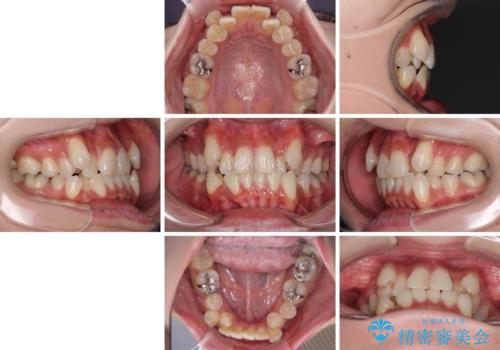

- 八重歯や前歯のデコボコを気にして来院された患者様です。

目立たない装置を希望されたので、上顎が裏側装置のハーフリンガルを選択し、上下左右の小臼歯(計4歯)を抜歯して矯正治療を行うこととしました。

補助装置を併用することで、八重歯を速やかに改善し、治療期間の短縮を図ることとしました。

ハーフリンガルでの矯正治療は、表側矯正よりも期間がかかることが多く、抜歯矯正では3年以上かかることも珍しくありません。

デコボコが強い一方で出っ歯ではなかったため、抜歯したスペースを容易に閉じることができ、短期間での治療となりました。